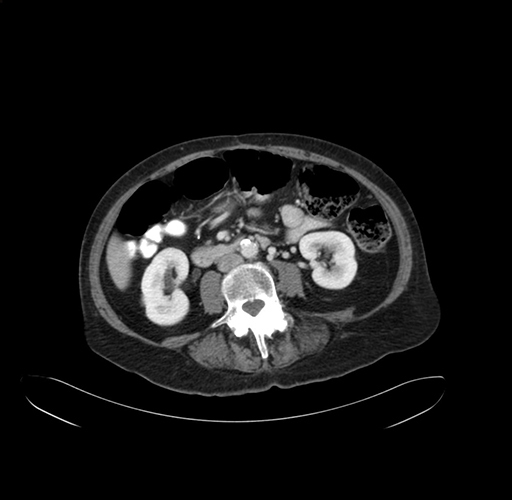

Axial Venous